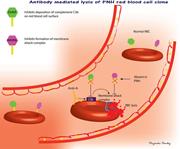

TRANSFUSION MEDICINE